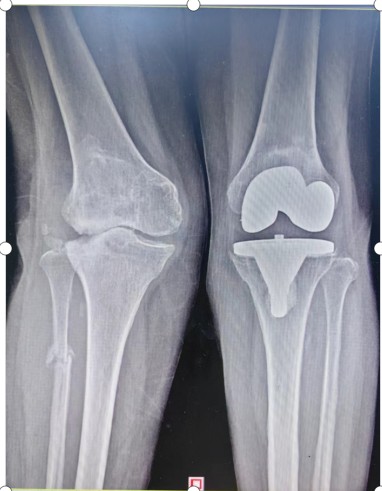

早在2015年,劉奶奶就因左膝關(guān)節(jié)重度骨性關(guān)節(jié)炎,在衡陽市中心醫(yī)院骨科二區(qū)進(jìn)行了左膝關(guān)節(jié)置換術(shù)。2022年6月,69歲的劉奶奶又因右膝關(guān)節(jié)疼痛畸形伴行走障礙再次入住骨科二區(qū)。劉奶奶右膝關(guān)節(jié)疼痛、畸形嚴(yán)重,必須依賴助行器行走。

入院后羅湘平主任醫(yī)師、彭健副主任醫(yī)生及蔣瀟純主治醫(yī)師查體時發(fā)現(xiàn)劉奶奶的右膝關(guān)節(jié)重度外翻,內(nèi)側(cè)副韌帶松弛嚴(yán)重致膝關(guān)節(jié)失去穩(wěn)定性。CT檢查發(fā)現(xiàn)右膝關(guān)節(jié)外側(cè)脛骨平臺缺損明顯,深度達(dá)1.5厘米以上,長期應(yīng)力異常,導(dǎo)致腓骨近端應(yīng)力性骨折。這種復(fù)雜膝關(guān)節(jié)畸形行人工膝關(guān)節(jié)置換不但技術(shù)難度大,而且費用很高。根據(jù)劉奶奶膝關(guān)節(jié)評估結(jié)果,可能需要行鉸鏈膝關(guān)節(jié)假體及金屬墊塊充填骨缺損,僅假體材料費用就要達(dá)6萬余元,普通家庭無法承受。

術(shù)前